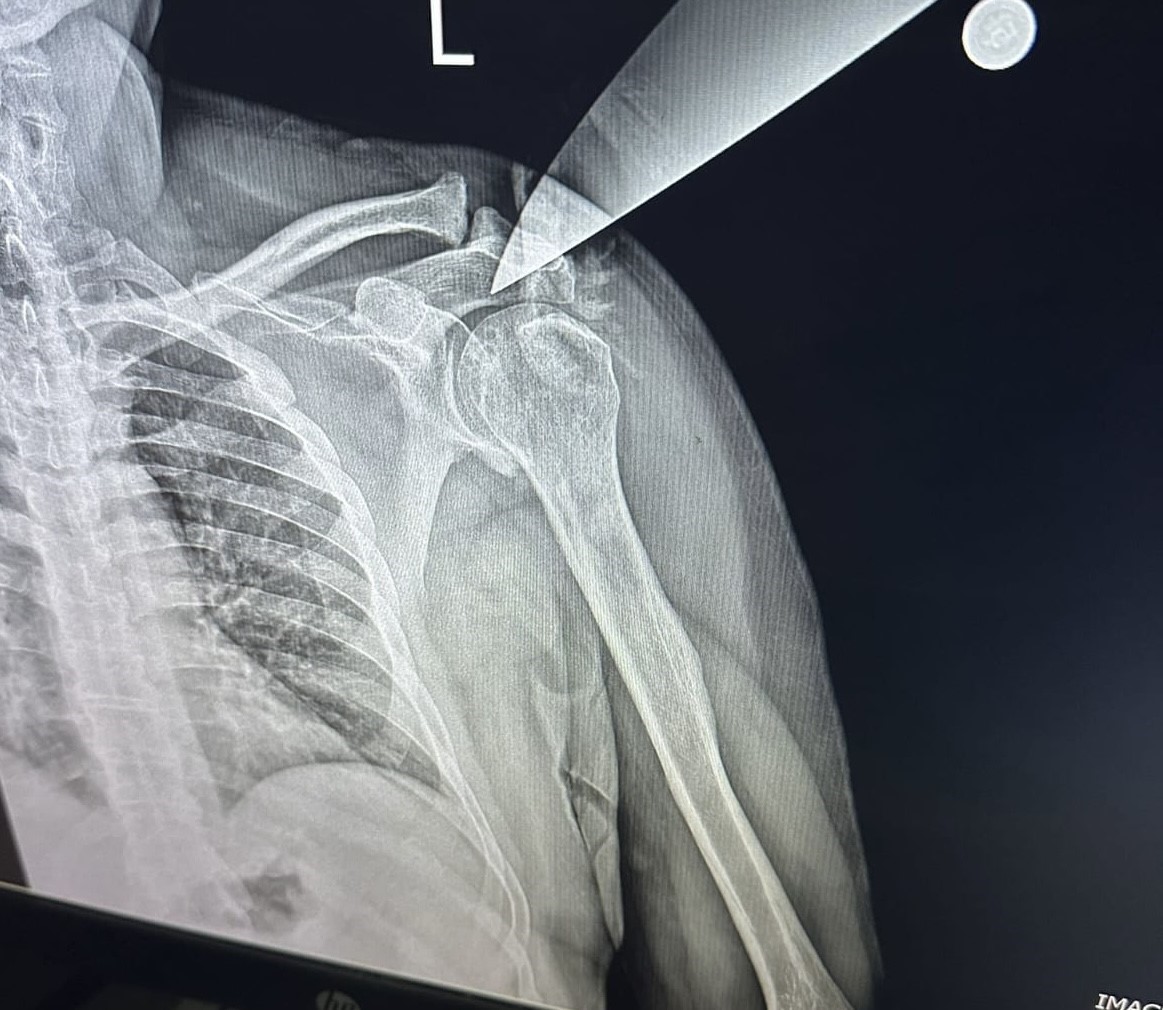

Bursa'nın Yıldırm ilçesinde 28 Aralık 2024'te özel bir diş kliniğine 3 çocuğuyla birlikte gelen H.H.Y. (25) adlı kadın, bir süre diş doktoru Hakkı Nail Ö. ile konuştu. Yoğunluk olduğu için alamadığını ifade eden doktoru arkasını döndüğü esnada çantasında taşıdığı bıçakla saldıran kadın, bıçağı Hakkı Nail Ö.'nün omzuna saplayıp çocuklarını da bırakıp kaçtı. Korku dolu anlar yaşayan doktor ve klinikteki meslektaşları, 112 ekiplerini aradı. İhbar üzerine olay yerine gelen sağlık ekipleri, yaralı doktoru Yüksek İhtisas Eğitim ve Araştırma Hastanesine sevk ederken, doktorun omzuna saplanan bıçak ameliyatla alındı.Tutuklandı